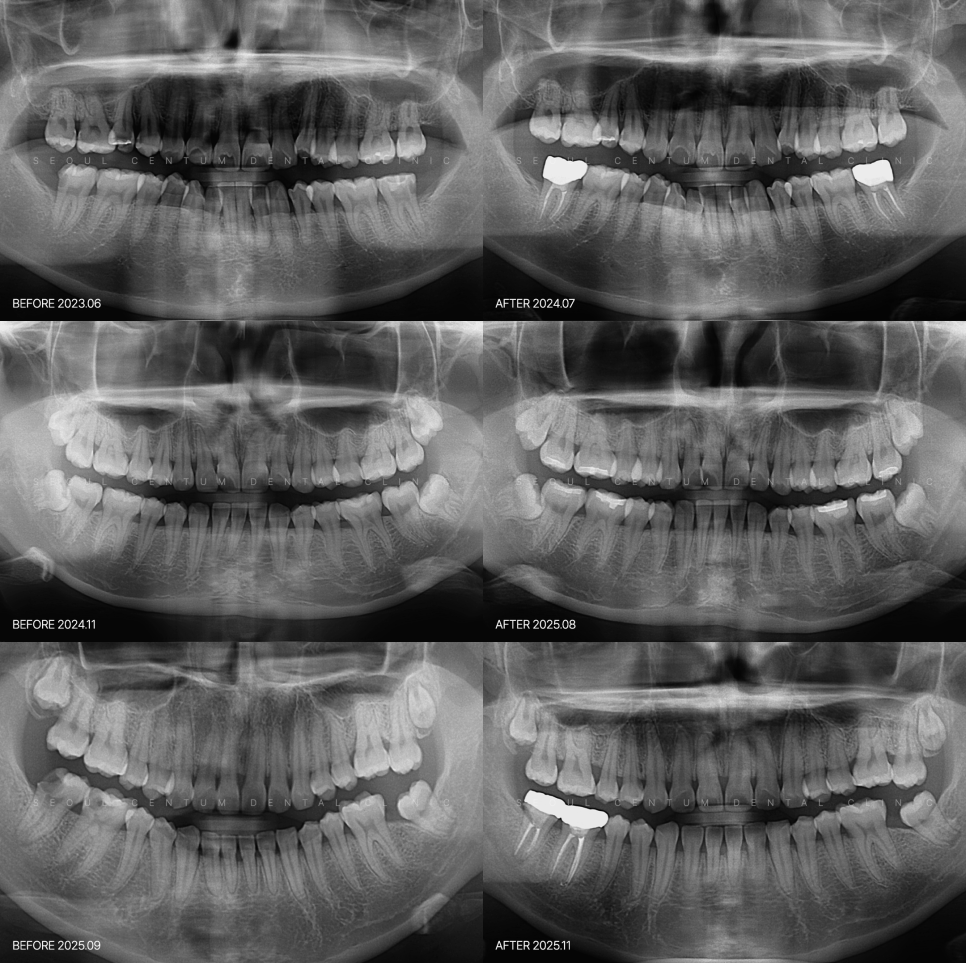

파노라마 엑스레이 촬영을 하면

훨씬 심한 상황으로 발견되는 경우가 많습니다.